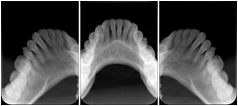

2. A patient requests cosmetic surgery to enhance their facial appearance. The case requires consultation between an orthodontist in New York and an oral surgeon in California. The cephalometric series of 2D projections constructed from the volumetric CT data that is used for the discussion is arranged by a Structured Display for transfer between the two practitioners.

Cephalometric Series Structured Display

Figure OO-2. Cephalometric Series Structured Display